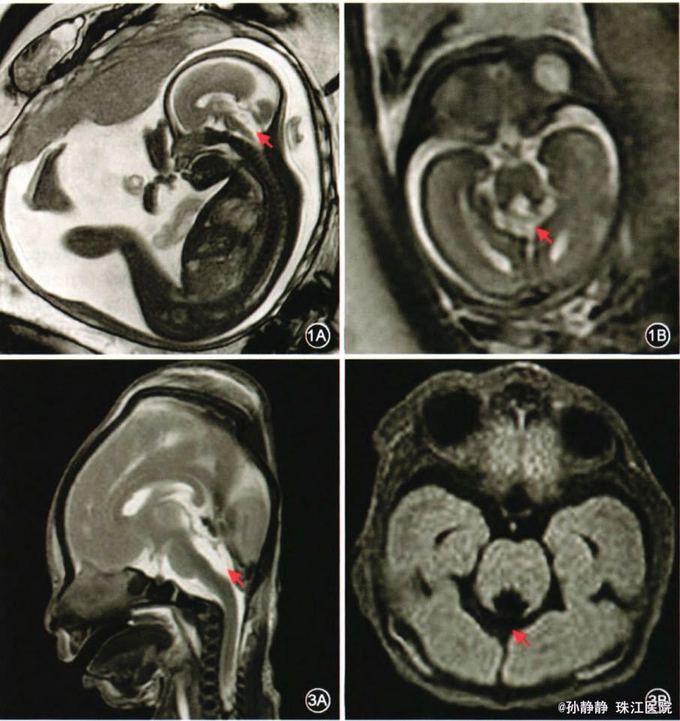

孕妇26岁,孕28周。孕25周超声发现胎儿小脑缺失可能。

孕27周MRI提示患儿小脑基本缺失,枕叶及小脑幕下移。

诊断:胎儿小脑缺失 处理:考虑预后不良,家属要求终止妊娠。引产后取胎儿脐血行微阵列比较基因组杂交技术基因分析未见染色体拷贝数增加或减少。